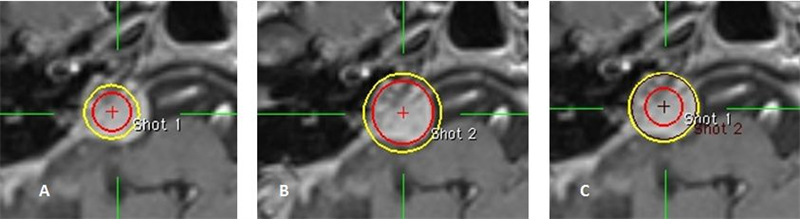

Hình 7: Hình ảnh A: Đường đồng liều không che phủ được hết khối u

B: Đường đồng liều vượt quá kích thước khối u

C: Đường đồng liều che phủ hết thể tích khối u

Bệnh nhân Trần Văn Th.; nam, 46 tuổi. Chẩn đoán: U dây thần kinh số VIII (P). Chỉ định xạ phẫu dao gamma quay (RGK) liều 14Gy”

Hình 8: Hình ảnh đặt 2 shot có tọa độ sát dần nhau

Bệnh nhân Đoàn V. H.; nam, 62 tuổi. Chẩn đoán: U màng não góc cầu tiểu não (P), chỉ định xạ phẫu dao gamma quay (RGK) liều 20Gy”

Mười kế hoạch trên cho thấy sự xuất hiện đường đồng liều 50% khi 2 shot 8mm được đặt gần kề nhau. Các hình cầu ban đầu hợp lại với nhau tạo thành “hình số 8” rồi dần trở thành một hình tròn đơn do sự tái chuẩn hóa.